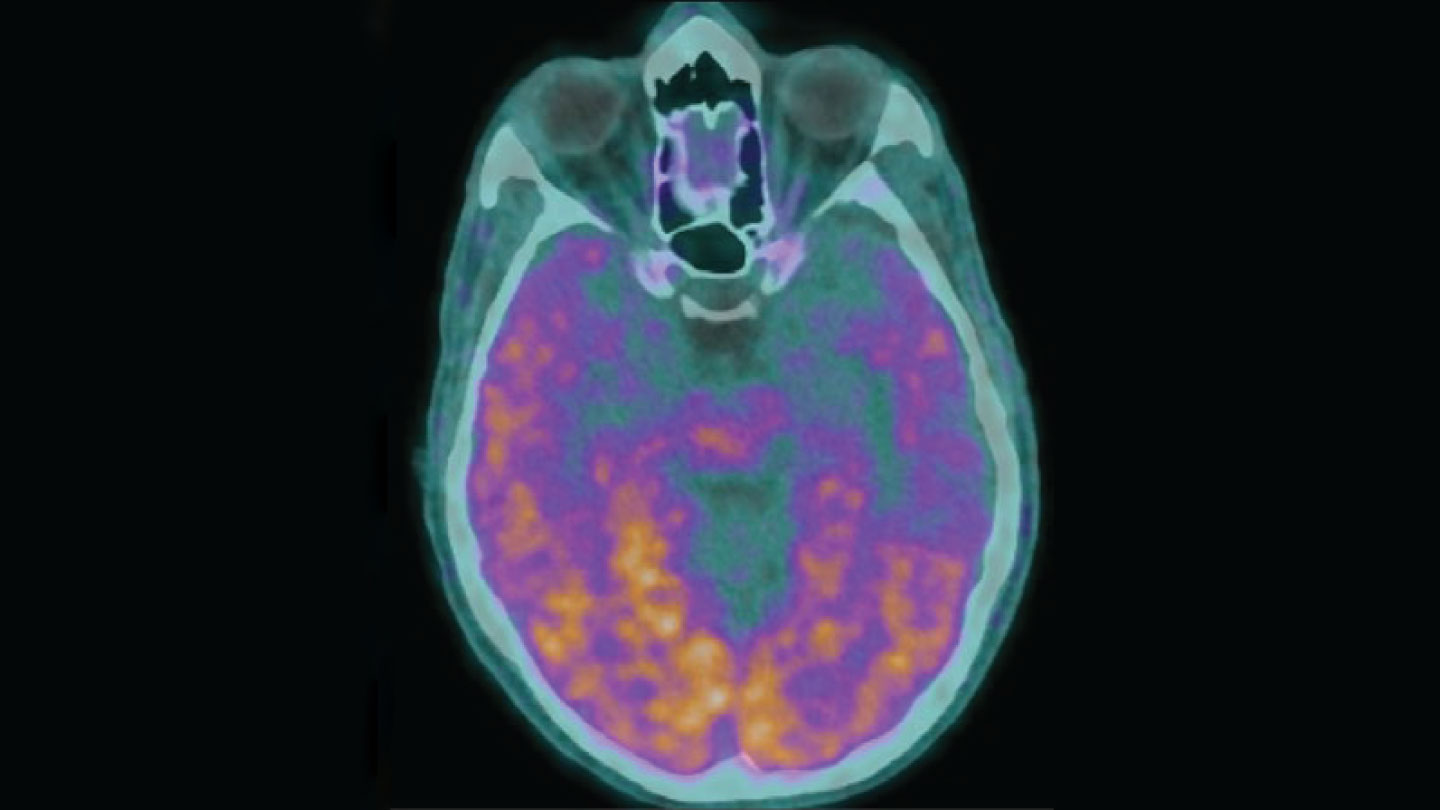

傳染性阿爾茨海默病?

阿爾茨海默病在日常生活中不會傳染,但在極其罕見的情況下,它會(SN:2/24/24,第 14 頁6)。研究人員表示,有五個人在童年時期接受了受污染的生長激素注射,後來患上了早發性阿爾茨海默氏症,很可能是因為這些激素受到了β-澱粉樣蛋白的污染,β-澱粉樣蛋白是一種與這種疾病有關的蛋白質。但其他專家指出,目前尚不清楚生長激素是否是罪魁禍首。也許這些激素旨在治療的健康狀況或其他醫療程序導致了這些患者患上阿爾茨海默氏症。